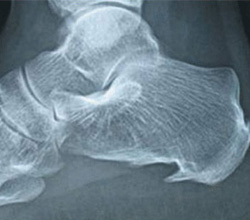

Tumoração do Calcâneo

Tumoração do CalcâneoTumores no tendão do calcâneo se apresentam como nódulos arredondados em suas fibras. Costumam ser indolores, causando apenas um incômodo discreto ao caminhar. O diagnóstico é obtido através de biópsia, mesmo que o indivíduo não tenha sintomas, é importante a avaliação médica para descartar possível infiltração em outras regiões do corpo. O tratamento consiste extirpação total da tumoração.